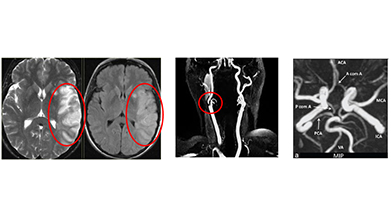

It is customary to also ask for MRI of the brain to look for areas of damage (infarct) along with MR angiography to look at all the 4 vessels in the neck and inside the skull including the formation of the Circle of Willis.

Prior to intervention it is customary to get either an CT angiography or a Digital Subtraction Angiogram (DSA) done to look at the location and extent of the disease segment as well as the collateral circulation in the brain.